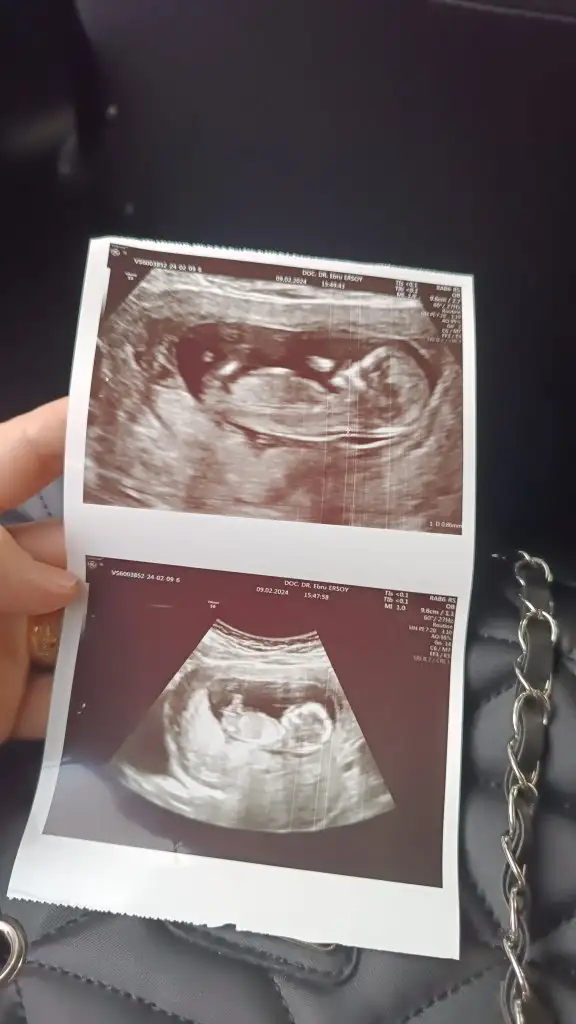

Sizce nedrYerleşim yeri erkek ama kemik yapısı kız. Bence minnoş bir kız olacak6-7 haftalık usg görüntüsü varsa ona da yorum yapayım

Bana yorum yapar mısınız lütfenYerleşim yeri erkek ama kemik yapısı kız. Bence minnoş bir kız olacak6-7 haftalık usg görüntüsü varsa ona da yorum yapayım

Ramzi teorisine göre de erkekbu teoriler sende tutmayacak sanırım

Yerleşim yeri erkek ama kemik yapısı kız. Bence minnoş bir kız olacak6-7 haftalık usg görüntüsü varsa ona da yorum yapayım